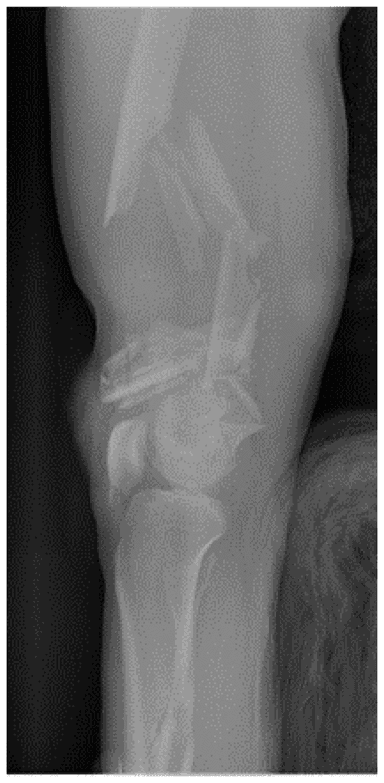

Зображення 6. Встановлення стержня у передпліччя.

Зовнішній фіксатор верхньої кінцівки, використаний при відкритому осколковому внутрішньосуглобовому переломі дистального відділу плечової кістки з ушкодженням плечової артерії внаслідок високошвидкісного вогнепального поранення. Було використано апарат зовнішньої фіксації швидкого застосування зі встановленням менших стержнів у дистальну третину променевої кістки та подальшим шунтуванням плечової артерії, після чого було виконано висічення та промивання поранень.

Примітка. На основі рентгенограми, виконаної після операції, було виконано корекцію стержня у дистальному відділі променевої кістки з огляду на його надмірне проникнення.

Зобр. 6a. Перелом дистального відділу плечової кістки із пошкодженням плечової артерії

Зобр. 6b. Рентгенограма стержня у дистальному відділі променевої кістки